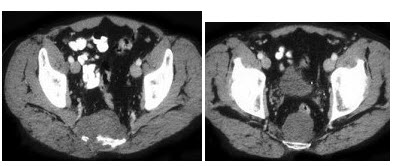

20、多项选择题

男,53岁,无痛性血尿2个月余,CT扫描如图示,下列说法正确的是()

A.右侧输尿管下段可见沿输尿管走行的软组织肿块影

B.软组织肿块边缘毛糙不平

C.其上方的输尿管扩张

D.考虑为输尿管移行细胞癌

E.考虑为输尿管内血块